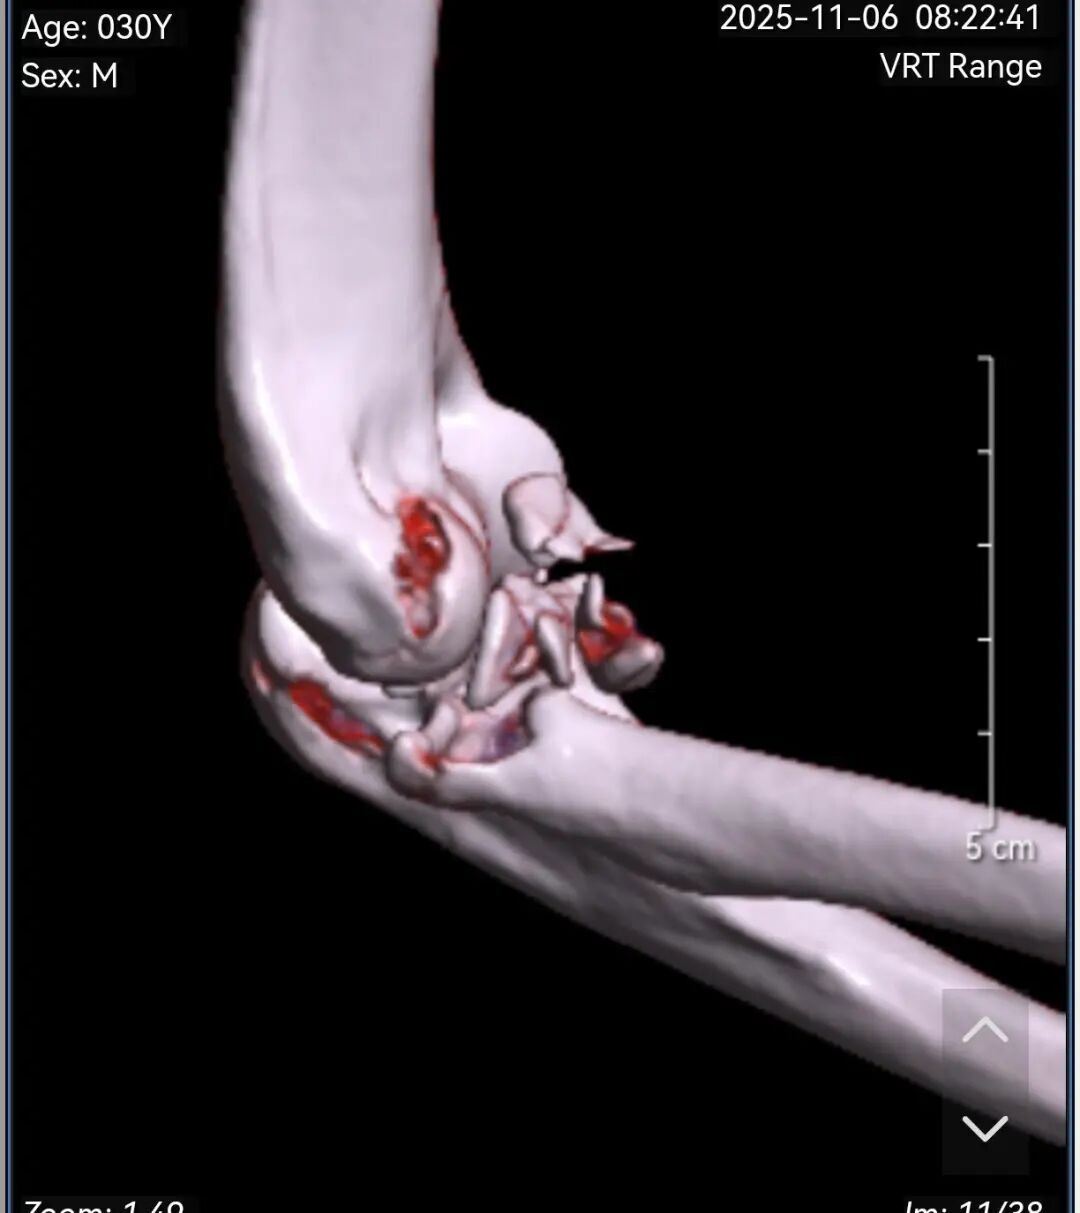

黄益平主任接诊后,经详细询问病史、查体并完善相关检查后,明确诊断为 “右肘关节恐怖三联征( 右尺骨冠突骨折、右桡骨小头粉碎性骨折 、肘关节后脱位已复位)”。

患者术前影像

黄益平主任随即带领骨科团队进行了全面的评估和讨论,结合患者伤情及影像学检查结果,制定了精准的治疗方案: 右肘关节恐怖三联征骨折切开复位内固定+韧带重建修复肘关节稳定术。

手术过程中,黄益平主任凭借精湛的操作技巧和丰富的临床经验,带领团队顺利完成骨折复位、内固定植入及韧带修复等核心操作,每一步都精准到位,环环相扣。

术后复查提示:骨折对位对线良好,内固定位置理想。目前,郑先生正在医护团队的专业指导下开展循序渐进的康复训练,肘部功能逐步恢复,预后良好。

患者术后复查影像